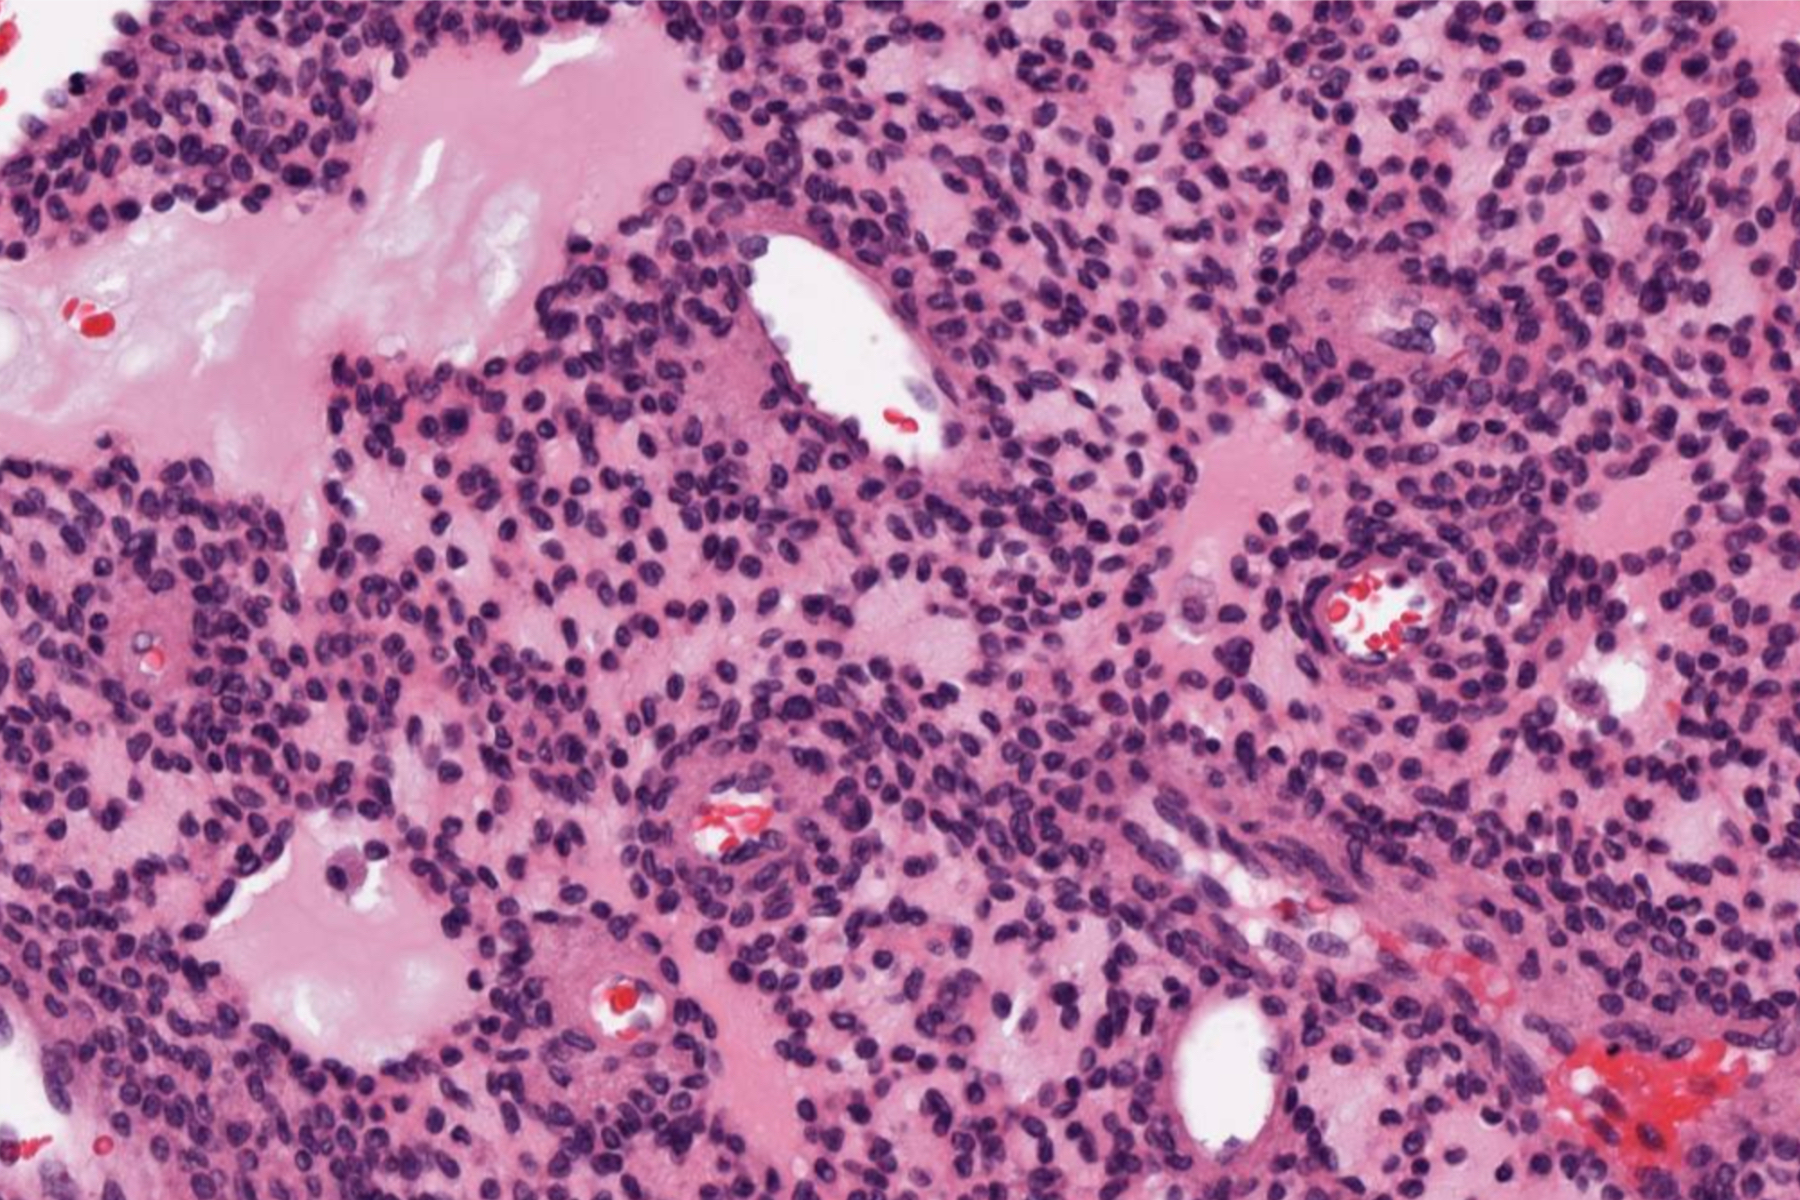

- 肿瘤细胞梭形及星状,疏松状排列,可产生特征性的“污浊”或絮状基质,常伴有钙化;

- 间质血管丰富,可呈血管外皮瘤样,由分化良好的分支毛细血管构成,有时呈海绵状血管瘤样;

- 常见破骨细胞样巨细胞。